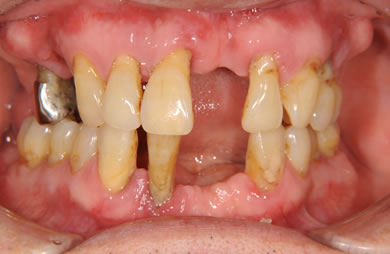

インプラントの症例写真 IMPLANT

骨再生スピードインプラント治療+AGC連結セラミック治療+セラミック治療

| 性別/年齢 | 男性 / 61歳 | ||||||||||||||||||||||||||||||||

| 主訴 | 歯周病の治療およびインプラント治療や義歯治療について相談したい。 | ||||||||||||||||||||||||||||||||

| 治療方針 | ソケットリフト法により上顎洞底部を拳上することにより、骨の無い部分に骨をつくってあげ、インプラント治療を可能にする。さらに歯周病により組織の破壊が著しいので、AGC連結セラミック治療により上顎の審美的回復を行う。 | ||||||||||||||||||||||||||||||||

| 治療内容 | インプラント7本(抜歯AGC即日スピードインプラント+ソケットリフト)、AGCハイブリッドセラミック連結ブリッジ1装置(上顎)ハイブリッドセラミック8本 | ||||||||||||||||||||||||||||||||